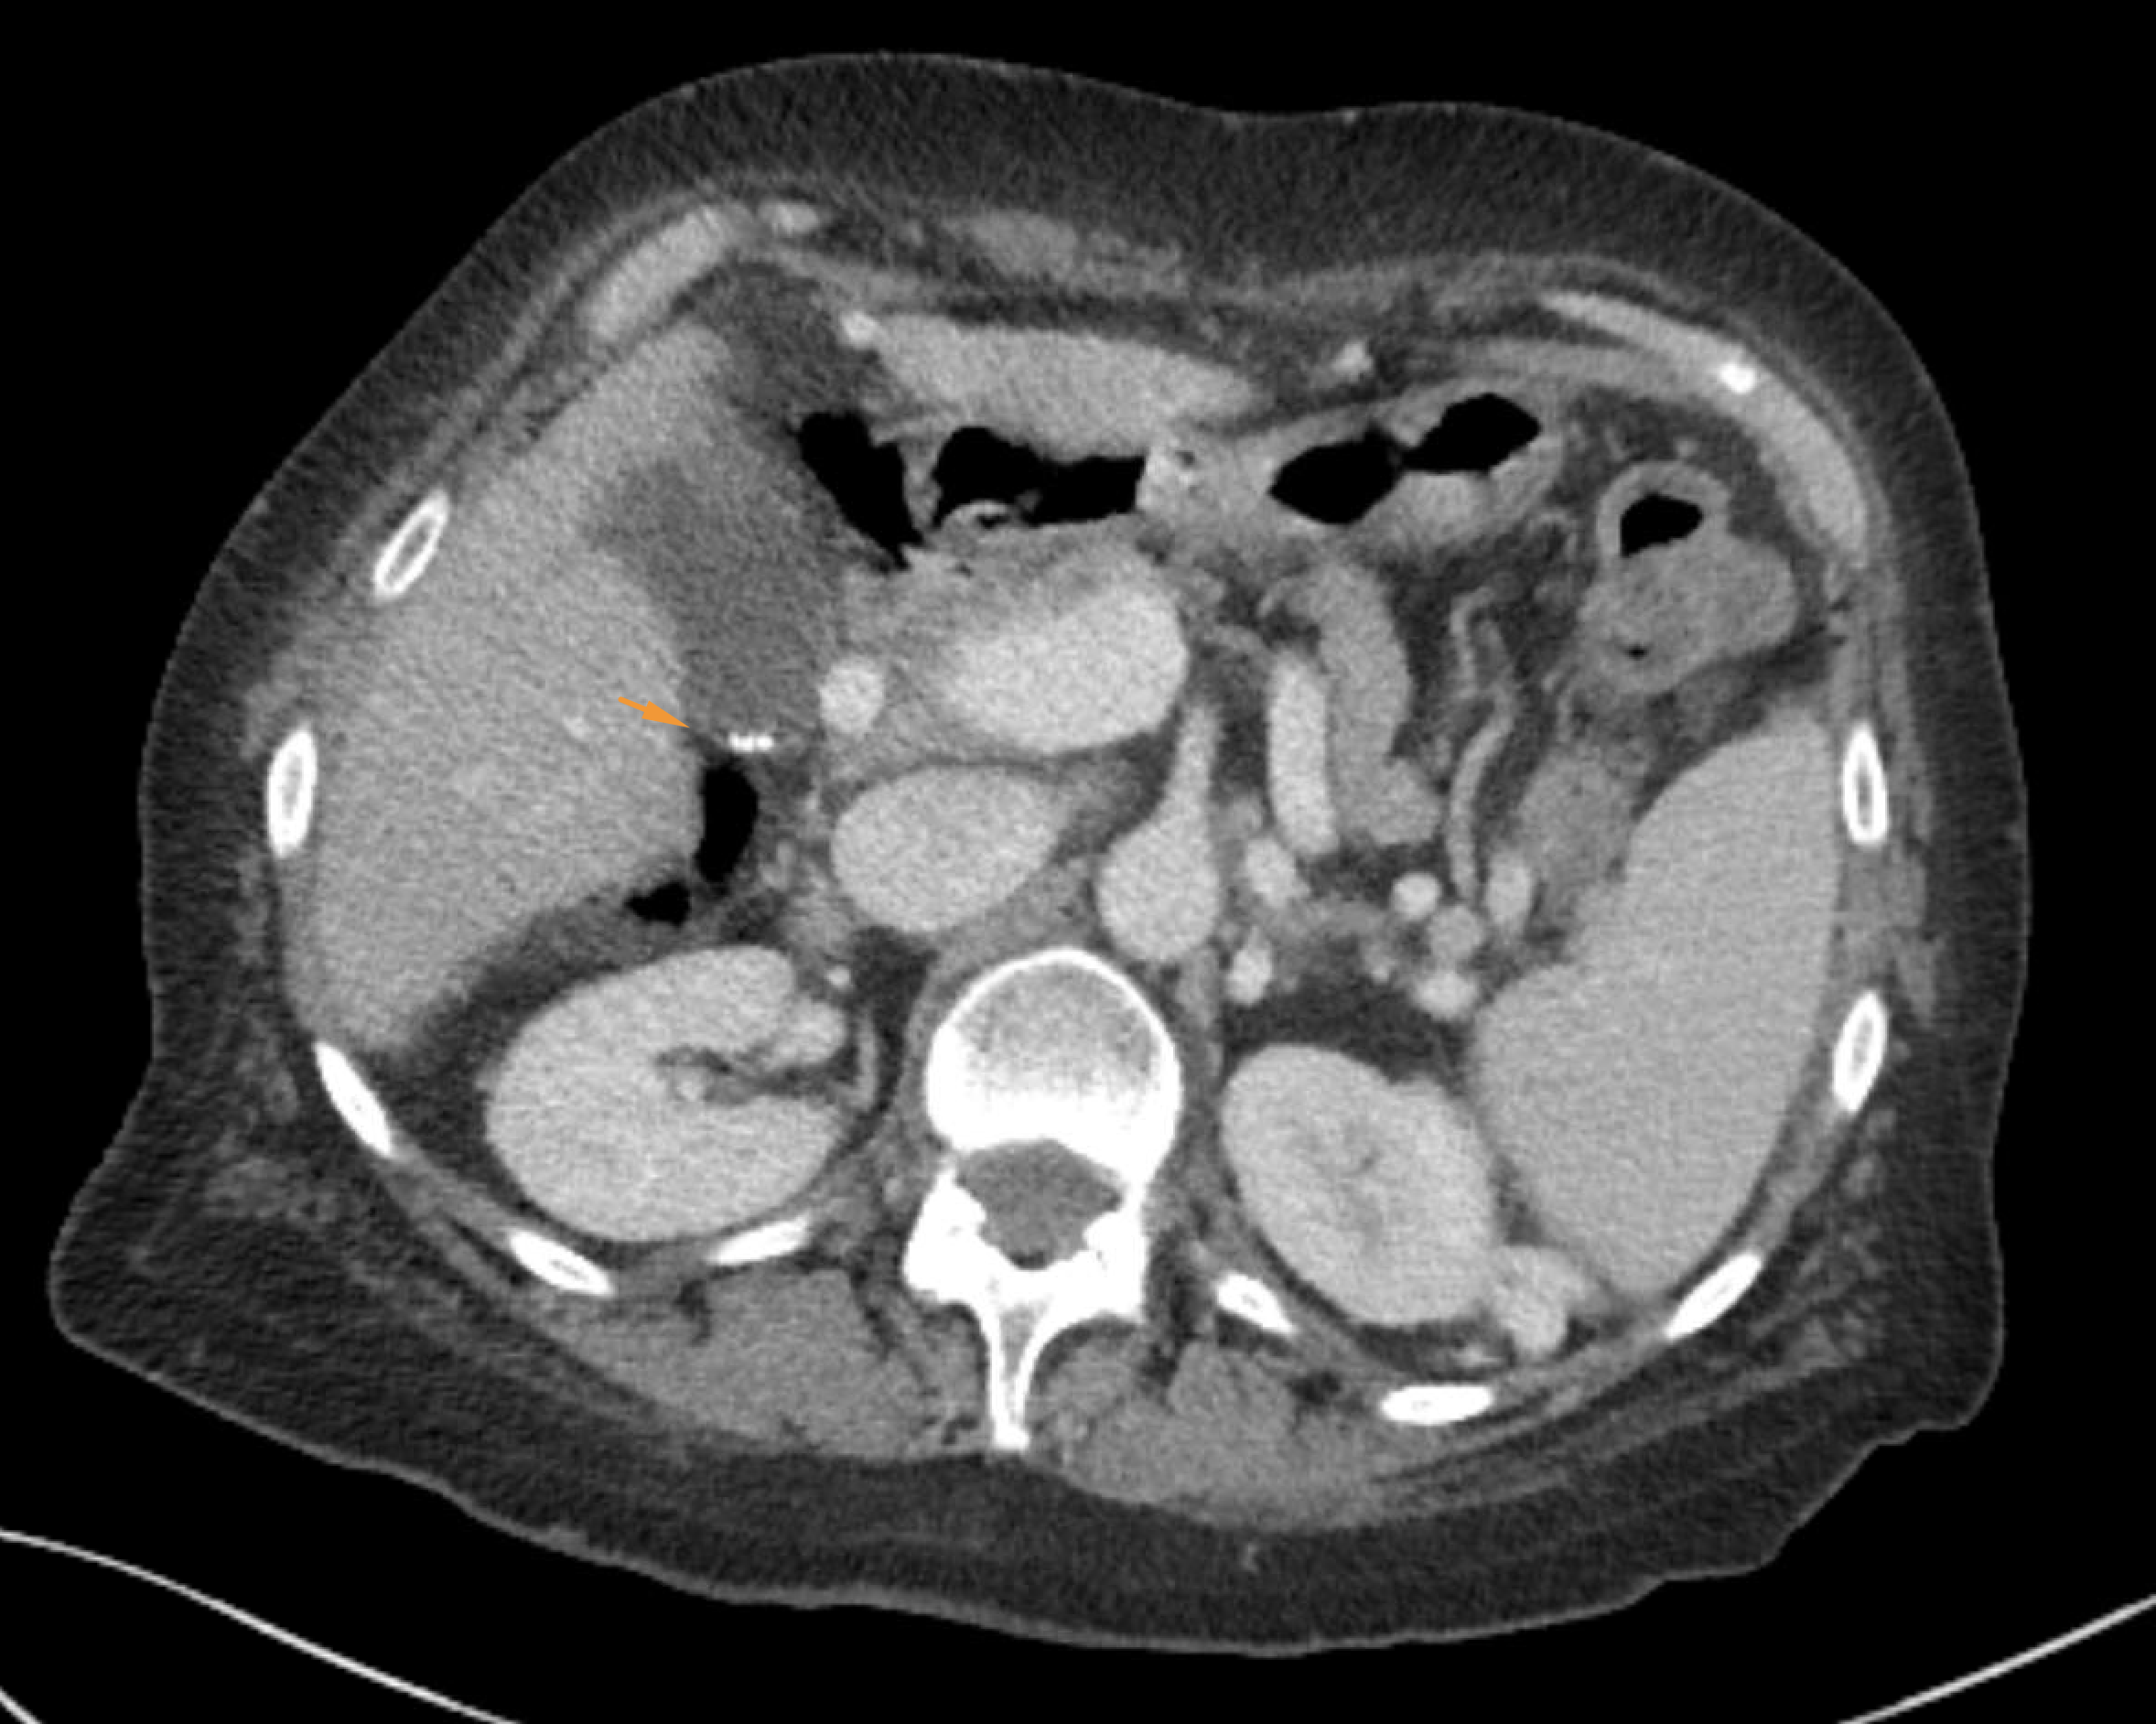

Age: 78

Sex: Female

Indication: Right upper quadrant pain

Radiotracer: Tc99m mebrofenin

Sample ReportNo evidence for acute cholecystitis. Patent biliary system.